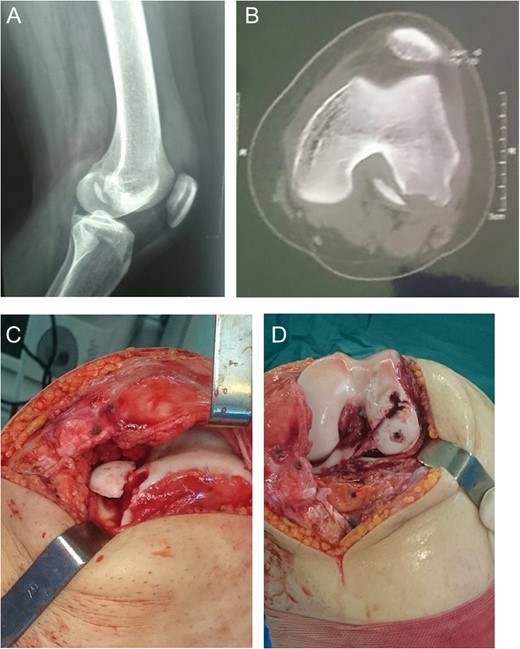

A 19-year-old male came with right knee pain and effusion after a non-contact injury of the knee during a football game. The knee had marked effusion with tenderness over the medial border of the patella. Radiography showed large OCF in the weight-bearing area of the lateral femoral condyle [Fig.1Aand B]. CT scan showed bony fragments from the medial border of the patella [Fig. 1C]. Three months after surgery, radiography showed complete healing of the injury with the full knee range of motion (ROM) [Fig. 1D and F].

Case 1. A and B Radiography showing lateral femoral condyle OCF. C, CT scan showing OCF and patellar avulsion fragment.D and E, 3 months postoperative radiography showing complete union.